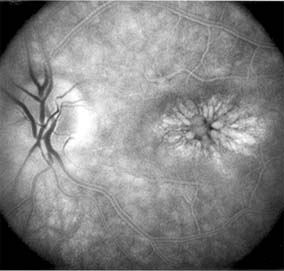

ANGIOID STREAKS

Angioid streaks appear as irregular, jagged tapering lines that radiate from the peripapillary retina into the macula and peripheral fundus (Figure 10-9). The streaks represent linear crack-like dehiscences in Bruch's membrane. The lesions are rarely noted in children and probably develop in the second or third decade of life. Early in the disease the streaks are sharply outlined and red-orange or brown. Subsequent fibrovascular tissue growth may partially or totally obscure the streak margins.

Figure 10-9

Figure 10-9: Multiple angioid streaks (arrows) extend from the optic nerve. (Courtesy of University of California, San Francisco.)